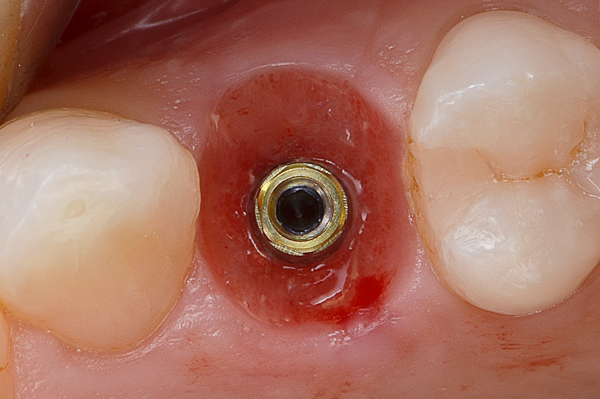

A seguito dell'analisi radiografica viene pianificata l'estrazione atraumatica del premolare con l'inserimento contestuale di un impianto Shelta. La riabilitazione immediata viene eseguita con un pilastro XA per protesi avvitata, su cui viene fissato un provvisorio realizzato in laboratorio secondo i principi dei profili di emergenza della tecnica B.O.P.T.